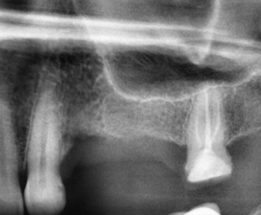

VarvaraLanina Опубликовано 3 января, 2022 Поделиться Опубликовано 3 января, 2022 Долго был разрушенный зуб - 4, не удаляла, потому что был опорой мосту и далее неизвестно как быть.. Удалили в прошлом мае, т.е. 8 месяцев прошло. Но с тех пор так и не проходят периодические ноющие боли в месте удаления и немного тянет к носу. Врач ничего не увидел "критичного". Посмотрите, пожалуйста фрагмент снимка. Спасибо. Ссылка на комментарий

It'sGeorgy Опубликовано 3 января, 2022 Поделиться Опубликовано 3 января, 2022 Добрый вечер. Немного смущает отмеченный участок. Сказать на 100% что это без КТ невозможно. 8 часов назад, VarvaraLanina сказал: далее неизвестно как быть Поставить два имплантата и восстановить жевательную функцию. Ссылка на комментарий

Irouil Опубликовано 3 января, 2022 Поделиться Опубликовано 3 января, 2022 Сделайте КТ, по приведённому снимку явных причин описанных жалоб не видно Ссылка на комментарий

VarvaraLanina Опубликовано 4 января, 2022 Автор Поделиться Опубликовано 4 января, 2022 спасибо. буду делать кт.. это может быть киста??? там кариес на клыке, сейчас собираюсь к стоматологу чинить его.. может ли он давать такое? Ссылка на комментарий